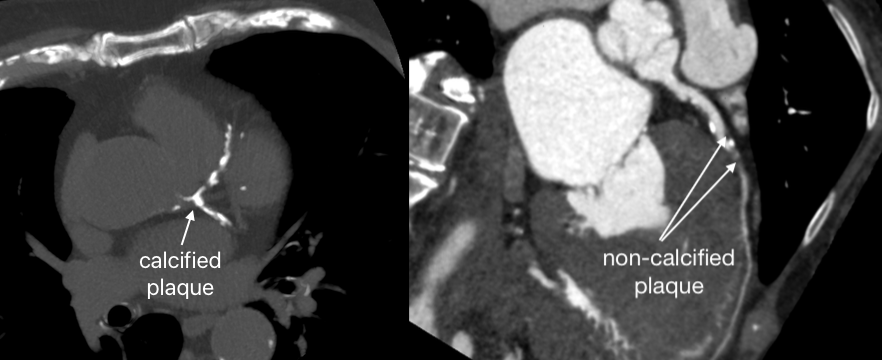

While a traditional calcium score measures the amount of mineralized (hard) plaque in your coronary arteries, AI-enabled plaque analysis looks at the "soft" or non-calcified plaque as well.

The primary limitation of a calcium score is that it only detects plaque that has already calcified. However, the most dangerous type of plaque is often "soft" or lipid-rich plaque. This type of plaque is more unstable and prone to rupturing, which is the leading cause of heart attacks.